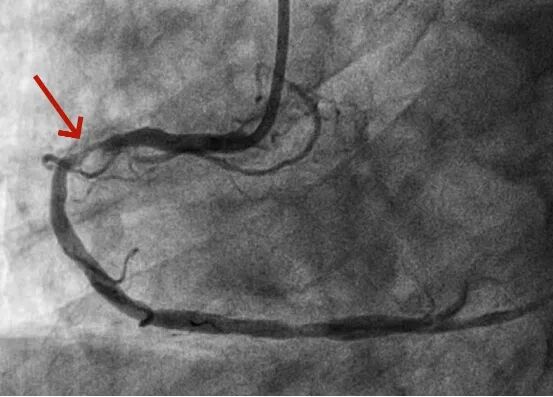

接到电话后,黔南州人民医院迅速响应,立即开通胸痛中心绿色通道,心血管内一科手术团队提前待命。患者抵达后,冠脉造影检查显示其心脏前降支血管近端完全闭塞,医护团队随即实施急诊手术,成功植入支架开通血管,患者转危为安。整个救治过程规范有序,术后患者恢复良好,无明显不适,目前病情已稳定。